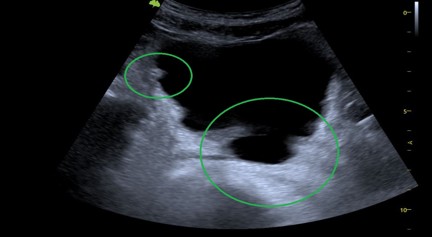

Uw huisarts is tevens opgeleid )* om eventueel, bij bepaalde klachten, een aanvullend echografie-onderzoek op de praktijk te doen. Dit zal nooit een totale buikecho vervangen, maar kan een richting geven in de beslisboom van de huisarts. Er zijn voor u geen kosten aan verbonden.

)* Nederlands Instituut voor Echografie in de 1elijn (NT-e).